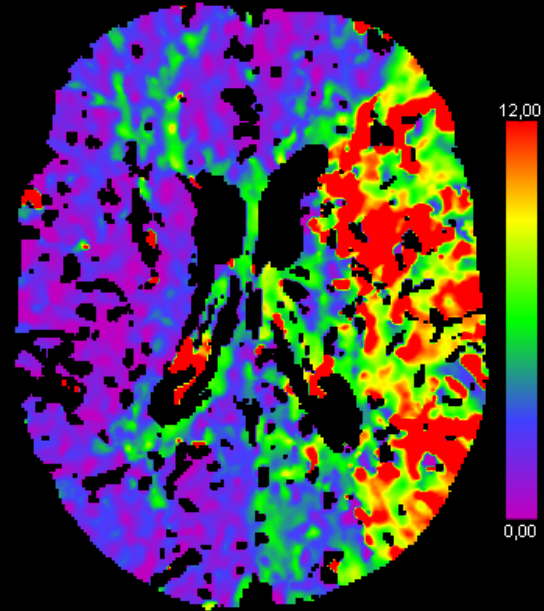

Den tekniske løysinga for betra bildediagnostikk er det Luca Tomasetti som har stått for. Hans del av tvillingprosjektet handla hovudsakleg om å utvikle nye automatiske metodar for bildediagnostikk ved hjelp av maskinlæring. Han har brukt bilete frå CTP-skanning (computertomografiperfusjon) som input for eit såkalla kunstig intelligens-nettverk som kan avgrense områda i hjernen med nedsett blodtilførsel. Med andre ord, skilje ut dei områda i hjernen som bør behandlast.

Forskinga til Tomasetti og Høllesli viser at bruk av bilete basert på CT-perfusjon som input for kunstig intelligens, og i tillegg bruk av nye og meir avanserte parameterar basert på CT-perfusjon, aukar moglegheita for å skilje ut og meir nøyaktig karakterisere dei slagramma områda.